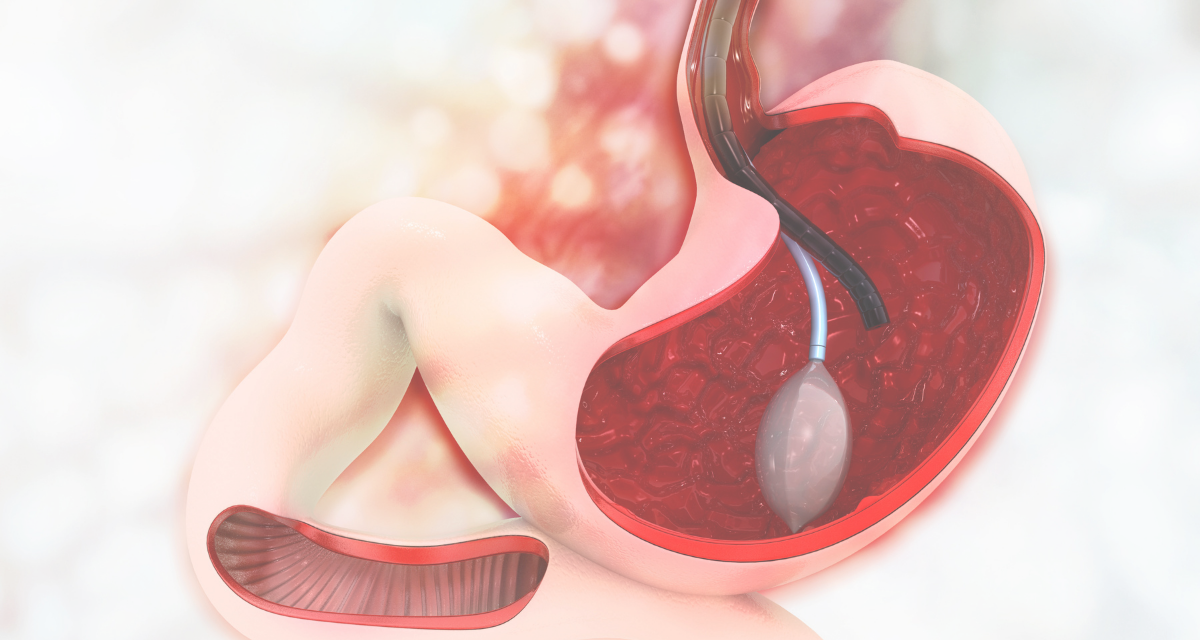

Желудочный баллон — это мягкий, гладкий и прочный баллон из силиконовой резины. Он предназначен для размещения в желудке, чтобы уменьшить его емкость и помочь вам чувствовать себя сытым при меньшем количестве еды. Сдутый баллон вводится врачом через рот в желудок с помощью эндоскопа.

Перед наложением баллона эндоскопически оценивают пищевод, желудок и 12-перстную кишку и выявляют наличие противопоказаний к наложению баллона. После удаления эндоскопа у пациентов без противопоказаний баллон через рот и пищевод через специальный аппарат направляется в желудок. Далее, после выравнивания положения баллона в желудке повторным проведением эндоскопии, баллон раздувают путем введения в баллон с помощью специального эндоскопического аппарата физиологического раствора, окрашенного метиленовым синим.